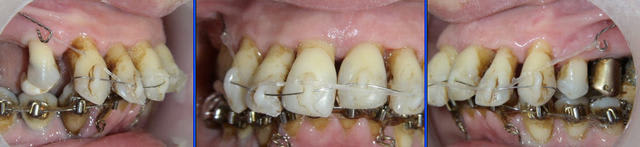

P.S. : je montre très prochainement une panoramique à 6 mois.

J'ai demandé expressément au parodontiste de me fournir des rétroalvéolaires. Comme il voit cette patiente mardi après-midi, il va en faire des toutes fraîches (vous aurez comme moi la surprise) et moi j'ai demandé à la voir juste après pour une nouvelle pano.. (je pensais ne la faire qu'en janvier, 1 an après le début, mais comme vous êtes pressés...).

A trois mois (photos f0), remplacement du fil élastique par un fil NiTi enfilé dans les lumières de composite. Un chaînette élastomérique continue la traction.

A six mois (photos f1, f2 et f3), résultats à ce stade et panoramique de contrôle.